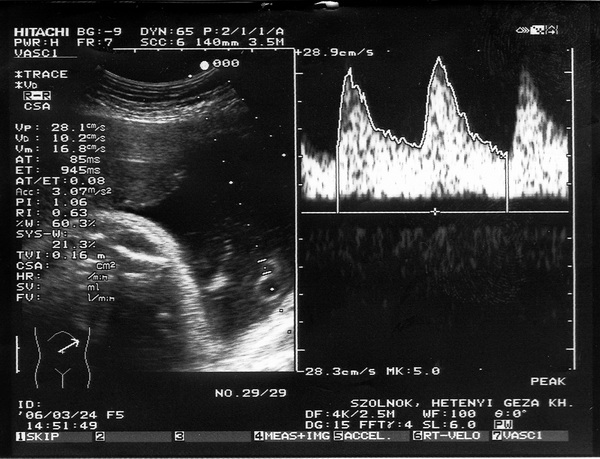

Én is voltam ma UH-n, legközelebb majd a kórházba megyek keringés vizsgálatra.